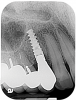

Based on clinical and radiographic examination of the area, the patient was diagnosed with moderate peri-implantitis subcategory A (Figure 10 and Figure 11).19 Pocket depths at this implant ranged up to 9 mm. A surgical approach was planned that included implantoplasty and guided bone regeneration.

Fig 11. Pretreatment radiograph demonstrating bone loss on the mandibular right first molar.

Figure 11